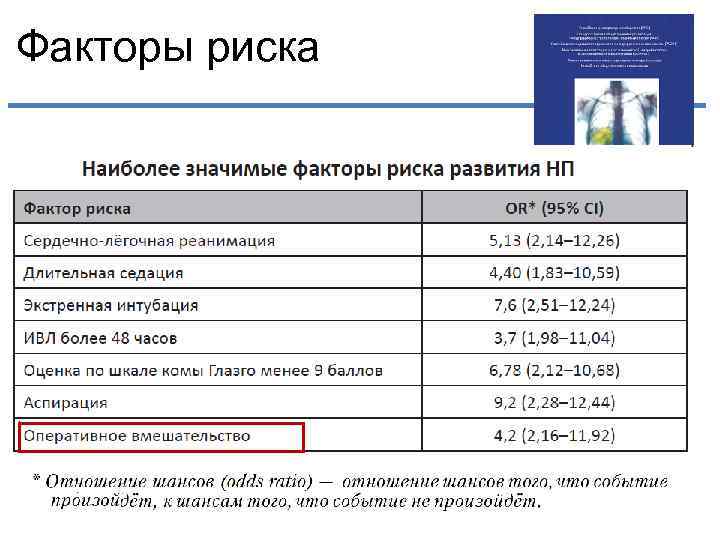

Факторы риска

Факторы риска

Факторы риска

Факторы риска

Факторы риска

Факторы риска